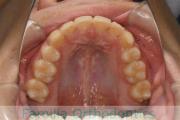

No.22V-409

- 叢生

- 16歳

- 女性

- 44

- 8|58

- FEA

- 86万円

八重歯を治したいということで来院されました。下あごの左ずれのある上顎前突(出っ歯)・叢生(でこぼこ)でしたので、上は左右から、下はで左のみ小臼歯を抜歯して、歯科矯正用アンカースクリューとマルチブラケット法にて治療を行いました。2年強、30回程度の通院が必要でした。

上下とも前歯の叢生(でこぼこ、凹凸、ガタガタ)があるため、保定を怠ると後戻りのリスクがあります。

- ≫治療前

上顎

下顎